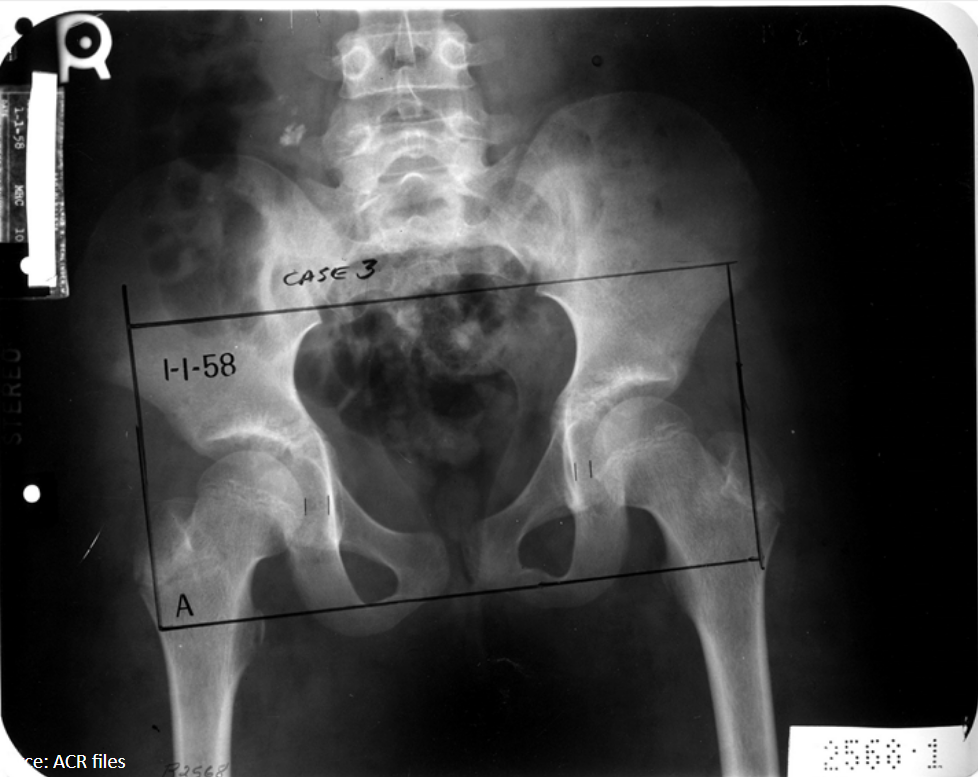

11

Q

What radiographic sign is present?

What does this mean by definition?

A

Waldenstrom’s sign: uneven hip joint space (one is increased) due to joint capsule swelling laterally displacing the femur

AVN of femoral capital epiphysis: LCP

12

12-year-old female presents with hip pain that refers to the knee.

Based on the evidence of avascular necrosis in her femoral capital epiphysis, what is the diagnosis?

Legg-Calve-Perthes (LCP)

Waldenstrom sign present

13

10-year-old female presents with a painful limp.

What is the diagnosis?

LCP

Legg-Calve-Perthes

sclerosis and flattening with epiphyseal fragmentation of femur (AVN)

14

What findings are seen in the right femur?

Mushroom deformity, degenerative changes, superolateral displacement of femoral head